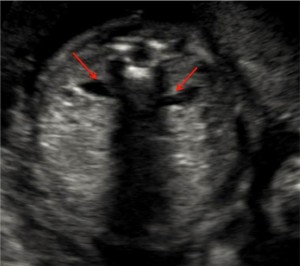

این تصویر مقطعی از سر جنین در سطح بطن مغزی جانبی در طول آزمایش در هفته 21 بارداری را نشان میدهد. اندازه گیری BPD (قطر دو طرفه)، HC (دور سر) و VP (شاخ خلفی بطن جانبی) باید دقیقا در این دیدگاه مغز جنین انجام شود. آناتومی مغز جنین نیز باید بررسی شود. فلش قرمز به خط اکوژنیک CNS متصل است که به طور معمول مغز را به دو نیمکره تقسیم می کند. فلش سبز به قسمت خلفی بطن جانبی اشاره می کند، که باید اندازه گیری شود (اندازه طبیعی کمتر از 10 میلی متر است).